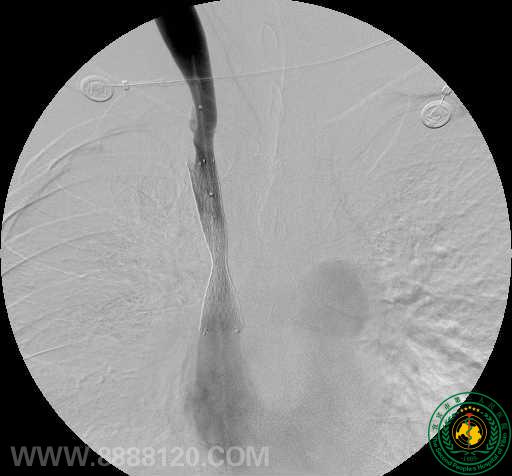

影像科介入组近日完成一例上腔静脉支架植入术

影像科介入组近日完成一例上腔静脉支架植入术3068